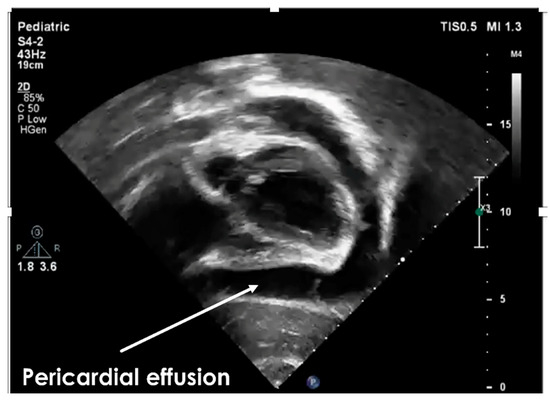

2. Case Report